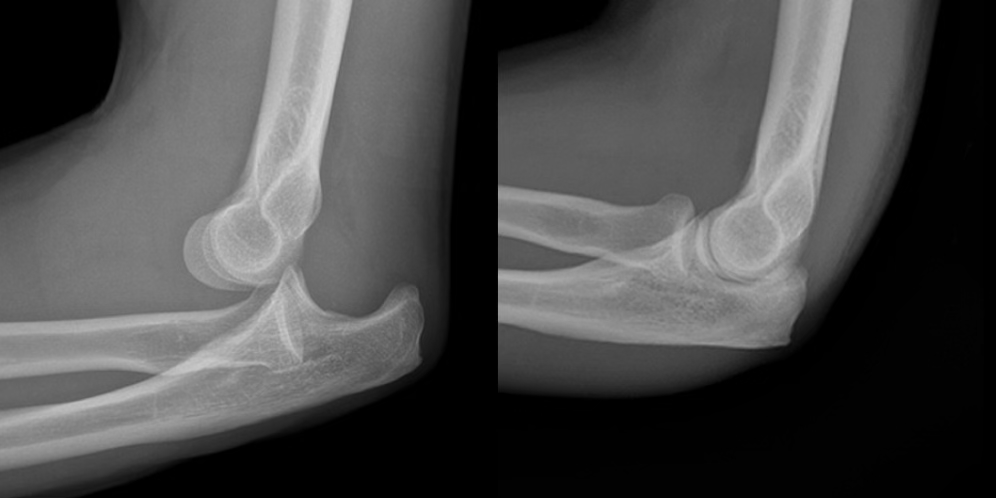

elbow fracture

FOOSH mechanism or direct hit

possible even incorrect reduction with elbow

symptoms of elbow fracture

swelling, muscle spasm, pain, possible deformity, reduced ROM, compromised neurovascular

treatment of elbow fracture

stabilize and ship

may need a sling or cast or surgery

depends on cast vs. surgery